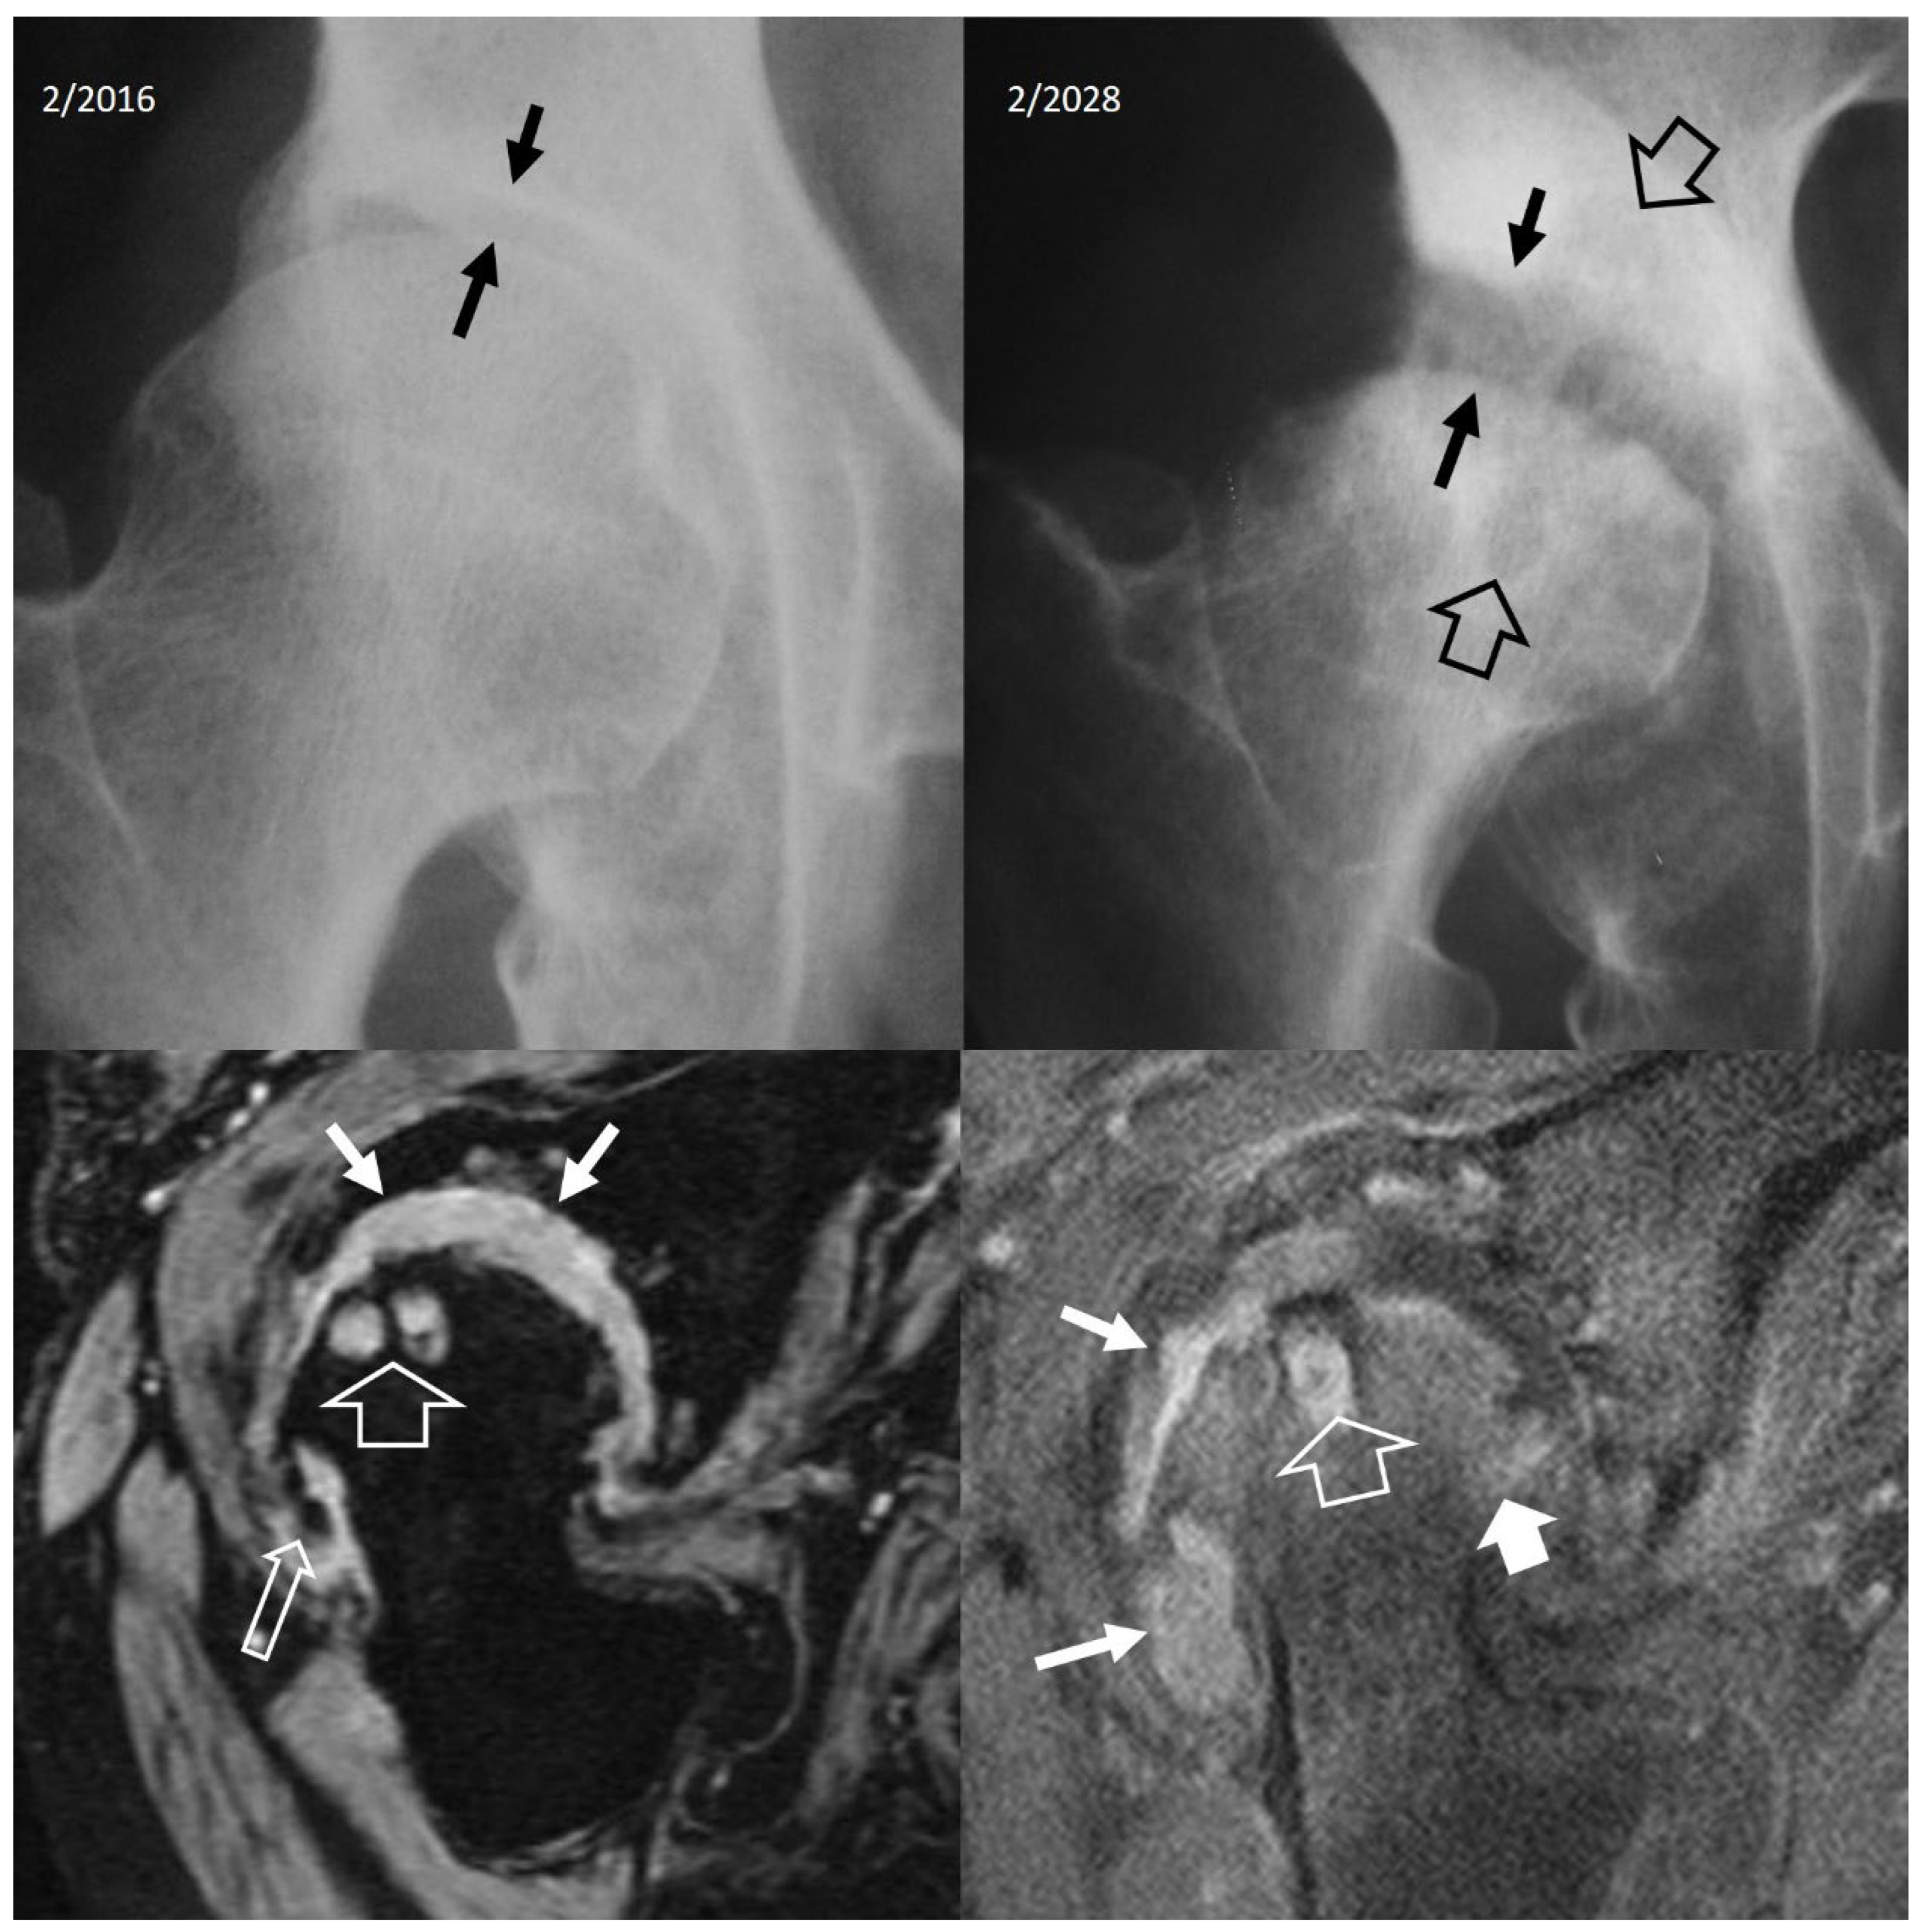

3. b.iv. Rapidly Destructive Osteoarthritis of the Hip

3. b.v. Neoplasms